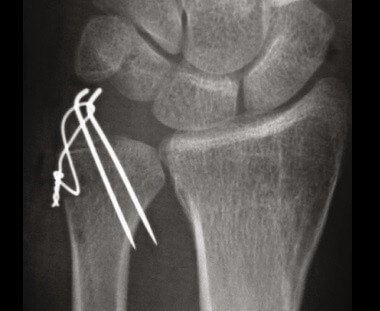

Ulnar Styloid Fracture Treatment: ORIF surgery for broken ulnar styloid

• Open Reduction and Internal Fixation (ORIF): An ORIF is the most common surgical method for treating ulnar styloid fractures. An incision is made near the fracture site and the bone fragments are repositioned (open reduction) and then secured with screws, plates, or wires (internal fixation).

• K-Wires (Kirschner Wires): For some ulnar styloid process fractures, temporary wires are inserted to hold the bone fragments in place while they heal. These wires are typically removed after the bone has sufficiently healed, usually in a few weeks to a few months.